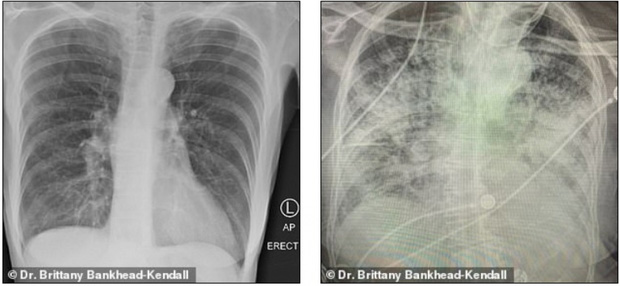

Bác sĩ phẫu thuật Brittany Bankhead-Kendall ở Trung tâm Khoa học Sức khỏe Đại học Kỹ thuật Texas (Mỹ) mới đây trưng ra 3 tấm phim chụp X-quang: Một của bệnh nhân khỏe mạnh, một của người hút thuốc, và một của bệnh nhân Covid-19.

Phim của người khỏe mạnh có nhiều khoảng đen, cho thấy họ có thể hít vào đủ lượng oxy cần thiết. Phim chụp phổi người hút thuốc thì có nhiều khoảng mờ, còn của bệnh nhân Covid-19 thì gần như trắng xóa.

Phổi người hút thuốc (bên trái) và phổi bệnh nhân Covid-19 (bên phải). Ảnh: Bác sĩ Kendall.

Những khoảng mờ trên phim chụp phổi thường là chỉ dấu của dịch lỏng, vi khuẩn, hoặc tổn thương và vết sẹo.

Bác sĩ Kendall đánh giá, phổi của các bệnh nhân trải qua Covid-19 tệ hại hơn bất cứ người nghiện thuốc lá nào mà bà từng biết.